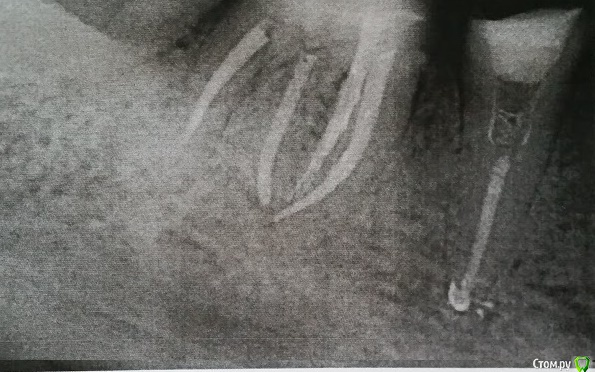

Анна Л. Опубликовано 22 января, 2020 Поделиться Опубликовано 22 января, 2020 Здравствуйте. Готовлю рот к имплантации, новым коронкам..При перелечивании 46 зуб треснул. Предложили гемисекцию.,Сама в раздумьях: её или сразу удалить? 1. Жалко, крепкий, без воспалений. 2. Каналы пролечены. Предложили объединить коронкой с 45. Корень будет (если) удаляться со стороны пятёрки,один из четырёх. Рядом живой 47. Что ещё останавливает от удаления (меня) - уже грядёт имплантация: 15, 35, 36, 11 и 22. А если будет ещё одно удаление, то это оттянет процесс минимум на три месяца, а и так уже времянки и дыры, организм уже устал, суставы.Плюс финансовая нагрузка повышается. Но если гемисекция,то самое большое опасение такое: 1. За пятёрку. Вдруг её потом расколбасит заодно. 2. За кость - может потом не на что будет ставить имплантат? Ну и за прикус. Правильнее вроде всё выставлять сразу. Хотя мостик 46-45 наверное для этого сгодится? Снимок просить постеснялась. Ссылка на комментарий